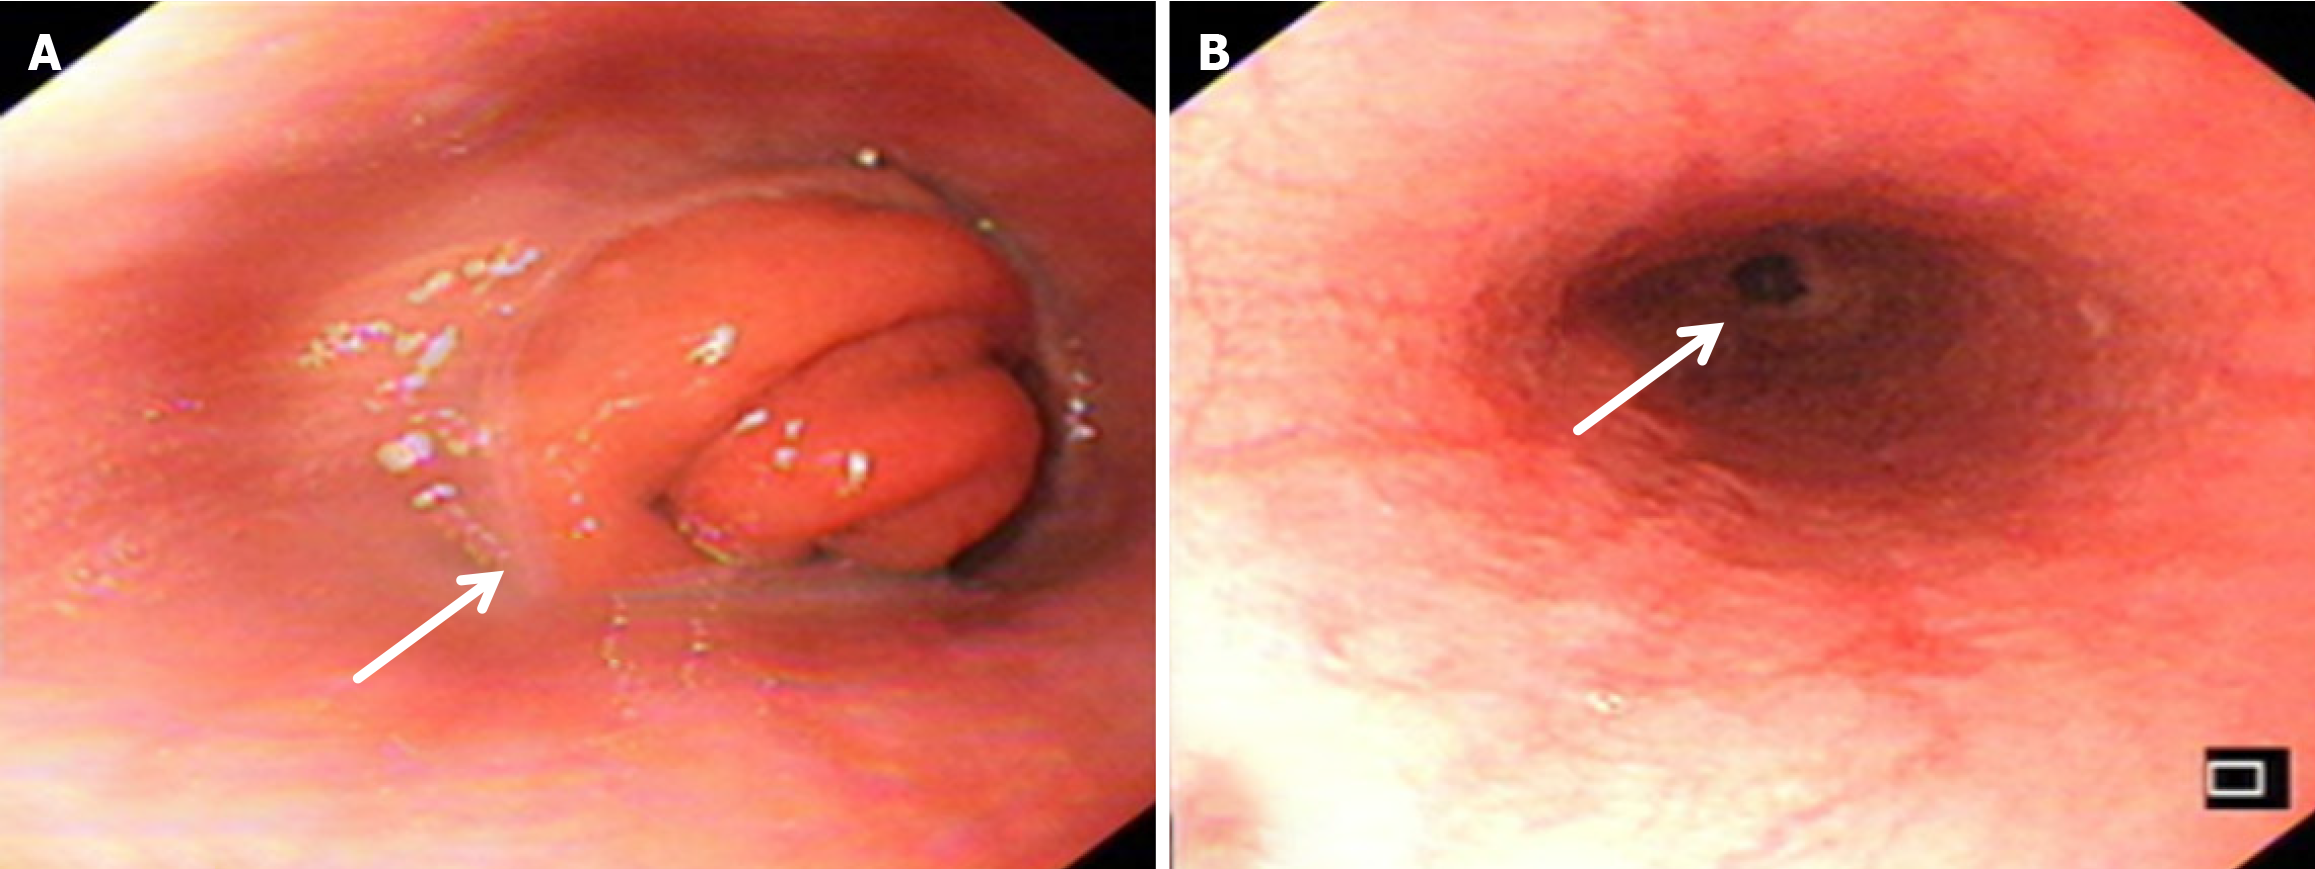

Compared with the modified group, the Orr group had a greater incidence of anastomotic leakage (AL) and short-term complications of anastomotic ischemia, although there was no significant difference between the two groups. Furthermore, Fisher’s exact probability analysis revealed that the incidence of reflux esophagitis, anastomotic ulcers by endoscopic examination, and intestinal obstruction in the Orr group was greater than that in the modified group at the 6-month postoperative follow-up period (P < 0.05) (Tables 3, 4 and 5).

There was no significant difference in weight loss between the two groups at 1 month after the operation (P > 0.05). However, in the improved group, the weight of the improved group was less than that of the original group at 3 months and 6 months after the operation (P < 0.05). The hemoglobin in the Orr group decreased significantly at 1 and 3 months after the operation compared with that in the improved group (P < 0.05), but there was no significant difference between the two groups at 6 months after the operation (P > 0.05). There was no significant difference in total protein or serum albumin between the two groups at 1 month, 3 months, and 6 months after the operation (P > 0.05) (Figures 2, 3, 4, 5 and 6, Table 6).

After total gastrectomy, due to the loss of antireflux function of the cardia, the reverse peristaltic wave generated by the pacing cells of the duodenum leads to the reflux of food and bile into the esophagus, resulting in clinical symptoms such as reflux esophagitis and other gastrointestinal duct discomfort[21]. Previous studies have shown that the jejunal storage bag after total gastrectomy can effectively relieve the pressure of food passing through the esophagojejunostomy. When food flows back from the distal output loop, the storage bag has a similar “siphon effect” to play an antireflux role and reduce the incidence of reflux esophagitis[22]. The antireflux effect is positively proportional to the length of the jejunal storage bag; nevertheless, a storage bag that is too long increases the incidence of Roux stasis syndrome, and the ideal length is approximately 5 cm[23]. In our study, storage bags with a length of approximately 5 cm were constructed at the anastomosis of the esophagus and jejunum in both groups. Our results revealed that the incidence of reflux esophagitis in the Orr group was greater than that in the improved group (P < 0.05), which occurred because the jejunal storage bag was constructed after the jejunum and its mesentery were disconnected, and the residual end of the storage bag lacked traction of the mesentery in the Orr group; therefore, the “siphon effect” was weakened. By contrast, the storage bag of patients in the improved group only needed to disconnect the jejunum, and the jejunal mesentery was continuous, resulting in strong negative pressure suction.